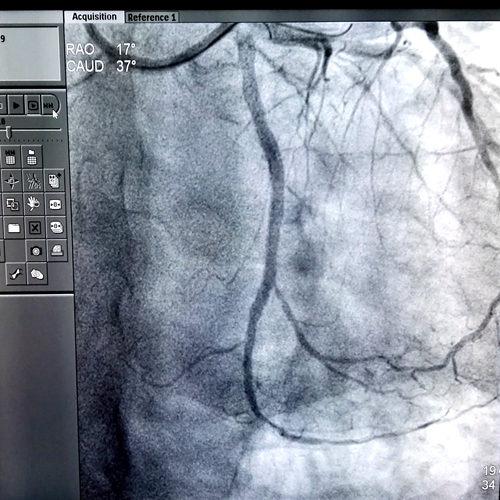

术后造影

接到电话后,范爱德副主任医师带领值班手术团队在最短时间内赶到手术室,在取得患者及家属同意后,17:20顺利完成冠脉造影+PCI术。造影显示:冠状动脉多支多处严重狭窄病变,其中左回旋支中段全部闭塞(考虑为本次心肌梗死的罪犯血管),球囊扩张后植入支架一枚,术后罪犯血管恢复正常血流灌注。整个手术顺利,从患者进入导管室到手术完毕仅用了1小时左右。